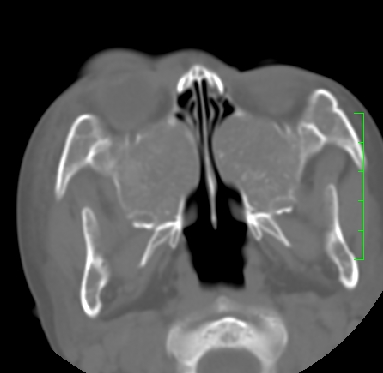

标题: PED1889:上颌窦病变

m,10y,外伤做ct